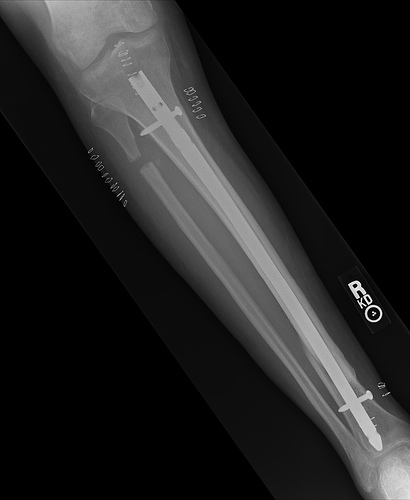

Tom: [looking at x-ray]: Blimey, that German has got a massive rod!

Fred: [pause] Tom, you mustn’t talk that way . . . [looks at x-ray] By Jove he does have a massive rod—in his thigh! It’s like a giant metal pin holding the bones together. I-I’ve never seen a thing like it!

That may not be exactly how we learned about the German invention of intramedullary rods, but so goes the lore among orthopedic surgeons. Intramedullary rods are long metal nails that surgeons use to stabilize and align certain types of fractures. The rod is inserted into the bone marrow, in the center of long bones (like the femur) and shares the load that the bone must support.